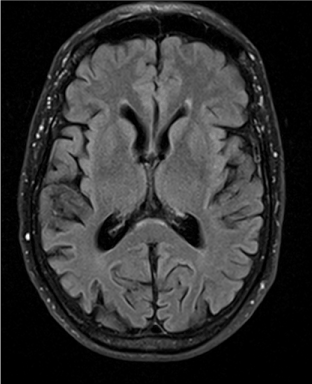

Four months later, the patient’s wife witnessed an episode of unresponsiveness from sleep. This occurred after technical problems prevented the patient from using his CPAP machine for the prior two evenings. The wife was initially awoken by gurgling sounds from the patient during the first half of the night and observed foaming at the mouth. The patient’s eyes were open, but he was not responsive to questions. During this event, he sat up and briefly spoke meaningless words, with deviation of the eyes and head towards the left. Bowel and bladder incontinence were not present. Emergency medical services were called, and the patient regained awareness during the ambulance ride to the hospital approximately 20 minutes after the beginning of the observed event. He was amnestic of the episode, and it was not associated with vivid dreaming. Subsequent evaluation of this event at the outside hospital consisted of an unremarkable MRI brain without contrast (Figures 1 and 2), normal 24-hour Holter monitoring, and normal routine EEG. As the patient’s exam and work-up were unremarkable, and this was his first episode of impaired awareness, no intervention was started.

Figure 1. MRI brain without contrast: Axial FLAIR.